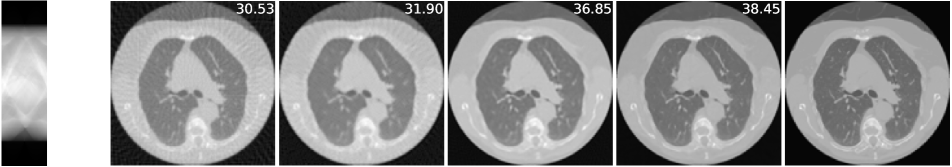

4.2 Sparse-view CT

The imaging physics model of X-ray computed tomography (CT) is the discrete radon transform. The physics model is the radon transformation where 50 views (angles) are uniformly subsampled to generate the sparse-view sinograms (observations) . The Filtered back projection (FBP) function, i.e. iradon, is used to approximate . In this task, we exploit the invariance of the CT images to rotations222It is worth noting that shift invariance is not useful for the CT case, as the forward operator is shift invariant itself (see Corollary 1)., and is the group of rotations by degree (=360). We use the CT100 dataset [33], a public real CT clinic dataset which comprises 100 real in-vivo CT images collected from the cancer imaging archive333https://wiki.cancerimagingarchive.net/display/Public/TCGA-LUAD which consist of the middle slice of CT images taken from 69 different patients. The CT images are resized to pixels and we then apply the radon function on them to generate the -views sinograms. We used the first 90 sinograms for training while the remaining 10 sinograms for testing. Note in this task, the supervised trained residual U-Net is just the FBPConvNet proposed in [12] which has been demonstrated to be very effective in supervised learning for sparse-view CT image reconstruction. We train our model with equivariance strength (see SM for more results and the equivariance strength effect). using the sinograms alone while the FBPConvNet is trained with the ground truth pairs .

A qualitative comparison is presented in Figure 4. The sparse-view FBP contains the line artifacts. Both the FBPConvNet and our methods significantly reduce these artifacts, giving visually indistinguishable results. Figure 5 shows the value of PSNR of reconstruction on the training measurements and test measurements and we have the following observations: (i) We would naturally expect the network trained with ground truth data to perform the best. However, we note that the equivariant test error is almost as good despite having no access to ground truth images and only learning on the sparse sinogram data. Furthermore the EI solution is about 7 dB better than the FBP, clearly demonstrating the correct learning of the null space component of the image. (ii) We note that there is a significant gap between training and test error for the FBPConvNet, suggesting that the network may be overfitting. We do not observe this in the EI learning. This can be explained by the fact that the EI constrains the network to a much small class of functions (those that are equivariant on the data) and thus can be expected to have better generalization properties.

We also compared the EI with its adversarial extension in (7) and the supervised learning regularized by equivariance objective. The quantitative results are given in table 1 below. First, MC learning obtains a small improvement in performance over FBP which may be attributable to the fact that FBP is only an approximation to . Alternatively it may be due to the inductive bias of the neural network architecture [34]. Second, the adversarial extension provides a slight improvement to EI and similarly the EI regularization helps the vanilla supervised learning obtain a further 0.6 dB improvement. These results suggest that it is indeed possible to learn to reconstruct challenging inverse problems with only access to measurement data.

| FBP | MC | EI | Sup | |||

|---|---|---|---|---|---|---|

| 50-views CT | 30.24 | 31.01 | 36.94 | 36.96 | 38.17 | 38.79 |